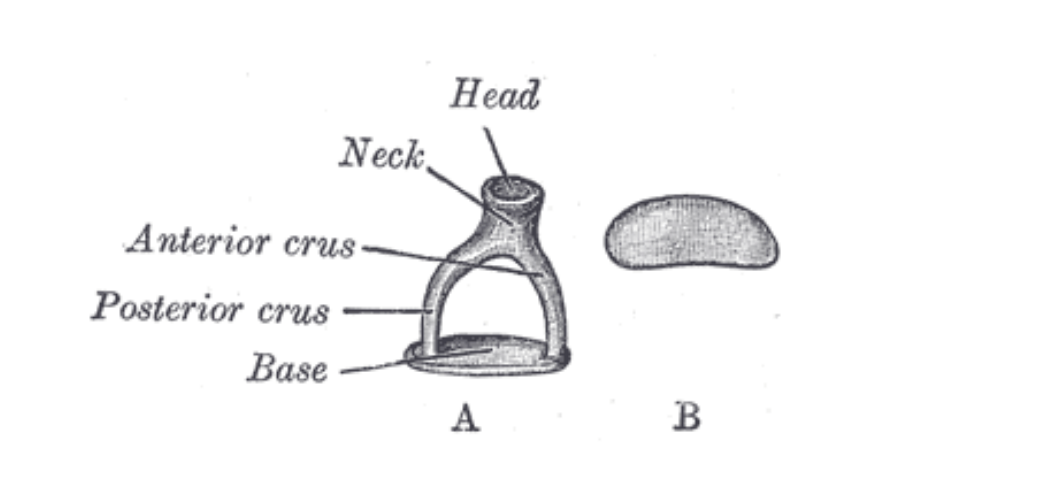

The Stapes